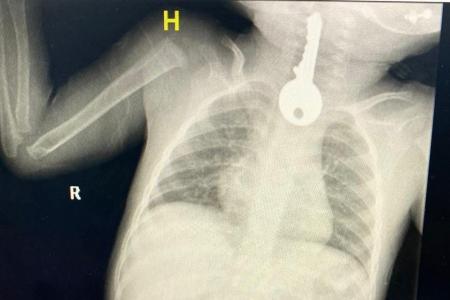

وعبر حسابه في "تويتر"، أوضح مجمع الملك فيصل الطبي أنه استقبل حالة طفل في وضع صحي حرج يُعاني من ضيق في التنفس مما استدعى تقديم الإسعافات الأولية وإجراء الفحوصات السريرية والإشعاعية التي كشفت وجود جسم غريب على شكل مفتاح في المريء.

وقال الفريق المعالج للحالة إنه تم على الفور عمل منظار عاجل واستخراج مفتاح حديدي من المريء كاد أن يودي بحياته ثم متابعته في قسم التنويم من قِبل الفرق التمريضية حتى استقرت الحالة وخرج بالسلامة ولله الحمد.